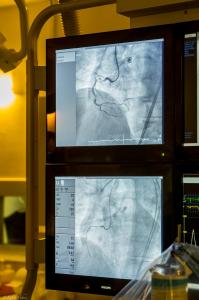

CTO Case 2017 Carmel Hospital Israel